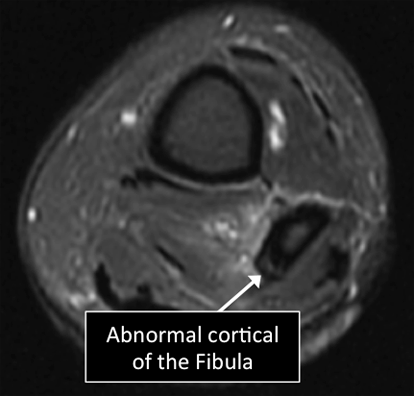

What is MRI used for in the bone ?

- MRI allows us to see many of the different structures in the bones.

- Several injuries or diseases affecting those structures can be diagnosed using MRI.

- Common things affecting bones include osteoporosis, tumors, fractures, osteoarthritis, among others.

Leg MRI examinations showing normal (top) and abnormal (bottom) cortical bone.

Why Translational MRI of the bone?

- In the bone, as in many other tissues of the body there are certain structures that can’t be seen (they look black or dark) with the standard MRI.

- There are new “software” programs that allow us to see structures with different contrast (bright versus dark).

- In the bone these “invisible” or dark structures include cortical bone, subchondral bone plate and vertebral endplate.

Leg MRI examinations using the standard MRI techniques (top) and translational MRI techniques (bottom).